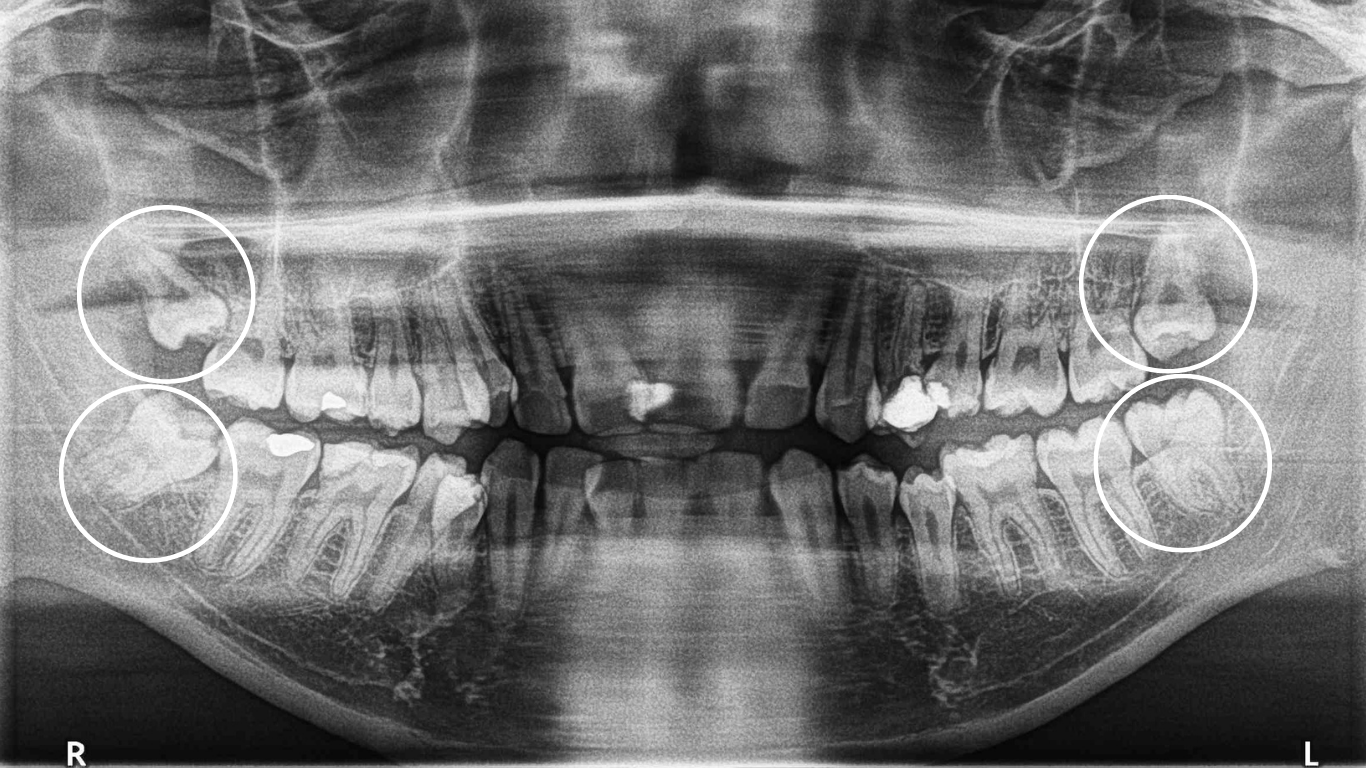

update your OPG imaging or get a CBCT if required

If you’ve already got an OPG x-ray less than 2 years old, upload it via the link below, share some health info, and get a free estimate from Dr Christine May within 24 business hours.